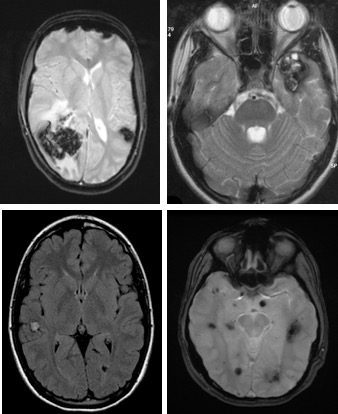

les cavernomatoses

le cavernome peut faire partie d’une cavernomatose familiale ; il existe 2 gènes connus. Il faut faire une IRM spinale pour s’assurer de l’existence de cavernomes médullaire. on ne traite que les cavernomes qui progressent et font craindre un risque hémorragique accru.

le phénotype est très variable au sein d’une même famille, avec souvent le parent atteint présentant peu ou pas de manifestations, et l’enfant révélant parfois qu’un de ses parents est porteur (anticipation). le plus souvent, on voit apparaître au fil des années de nouvelles lésions (soit que des lésions qui étaient jusqu’alors infra-radiologiques progressent, soit que l’imagerie s’améliore), mais sans incidence clinique (cf. ci-dessus). l’évolutivité est donc variable mais en règle générale, après un début aigu, on n’observe que très rarement un nouvel épisode cliniquement significatif.

le comportement d’un cavernome n’ayant pas saigné est imprévisible. le risque de saignement chez l’adulte a été évalué à 0,1% par an et par cavernome. il est probablement supérieur chez l’enfant. les cavernomes localisés en fosse postérieure sont plus agressifs, avec un risque de resaignement de 10% par an environ.

en cas de cavernomatose, on ne traite que les lésions symptomatiques ou à risque important de resaignement (en particulier en fosse postérieure).